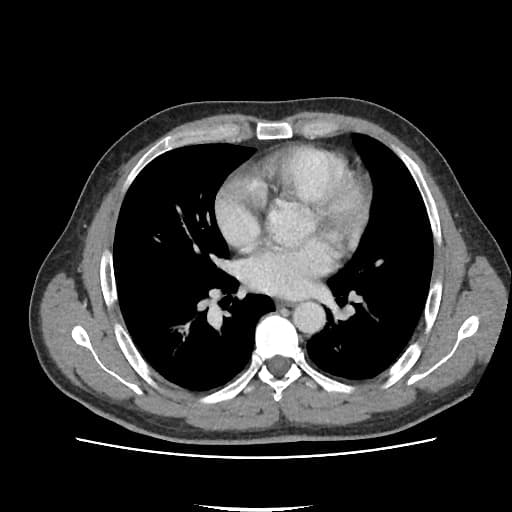

CT